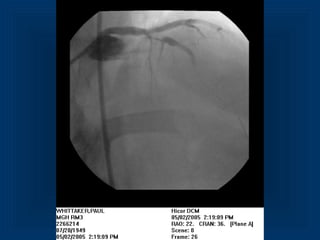

• Patient withcrushing chest pain • now relieved (Nitro) • Borderline ST- Elevation • No biomarker elevation Patient with ACSPatient with ACS

• 27.